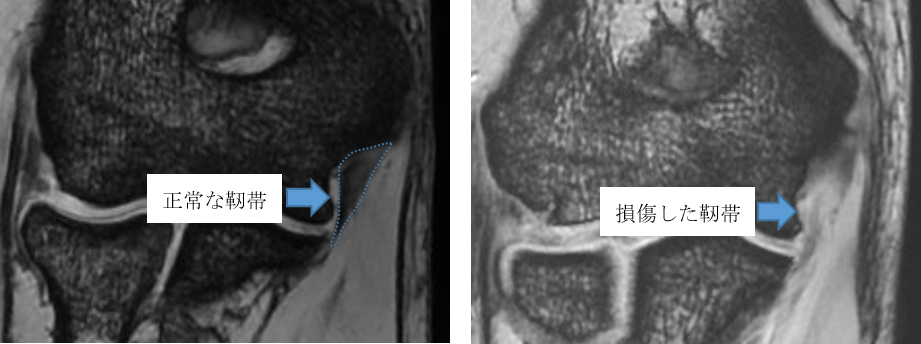

内側側副靭帯(尺側側副靭帯:UCL)は、肘の内側に張る靭帯で、投球動作など肘関節がしなる際にしなりすぎないように働く靭帯です(図1)。近年、プロ野球選手やメージャーリーガーでも多くの選手がUCL損傷を発症し、手術的治療を行ったことが報道されています。初発で靭帯損傷が軽度であれば手術を行わず、リハビリで復帰することも可能ですが、靭帯損傷が高度であれば手術的治療も考慮します。保存療法成績は,42%~84%と報告されています。

当院の調査では、内側上顆に学童期の遺残裂離骨片を有する症例(図2:リスク2.6倍),MRIでの完全損傷(図3:リスク4.6倍)を有する症例が手術を要するリスクが高まることが分かっています。詳細な評価に基づく診断を行い,3ヶ月以上のリハビリテーションを主体とした保存療法を行っても競技復帰が達成できない場合は手術療法を考慮します。手術を行う条件として,選手が競技復帰・継続を強く希望することが必須となります。

【図3 MRI検査でのUCL】